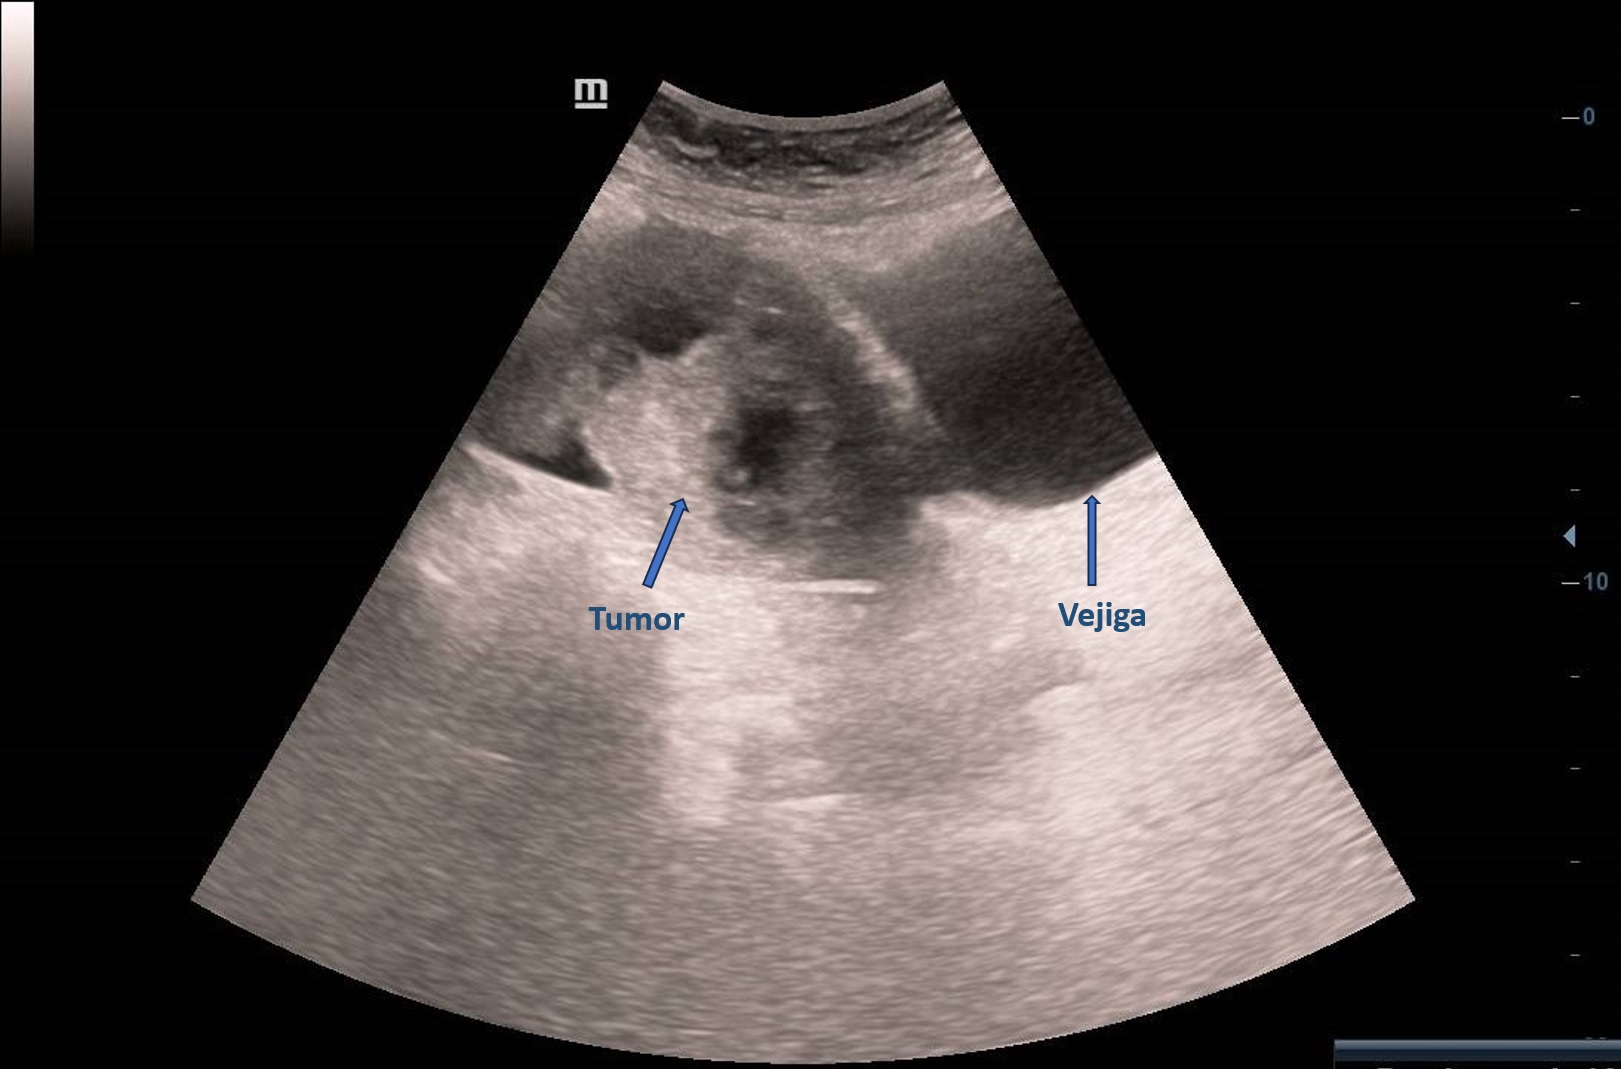

Ecografía abdominal en Atención Primaria: masa derecha adyacente a vejiga, vascularizada, de ecogenicidad heterogénea de unos 6 cm sin quedar clara dependencia del ovario derecho con imagen hipoecogénica en pelvis sugerente de ascitis. Se deriva paciente a ginecología preferente donde se realiza ecografía transvaginal: Tumoración anexial derecha, contorno irregular sugerente de neoplasia.

El EO se puede clasificar como benigno o maligno dependiendo de las características histológicas. En la ecografía aparece como una masa sólida heterogénea. No existen características ecográficas distintivas exclusivas. Ocasionalmente hay ascitis.